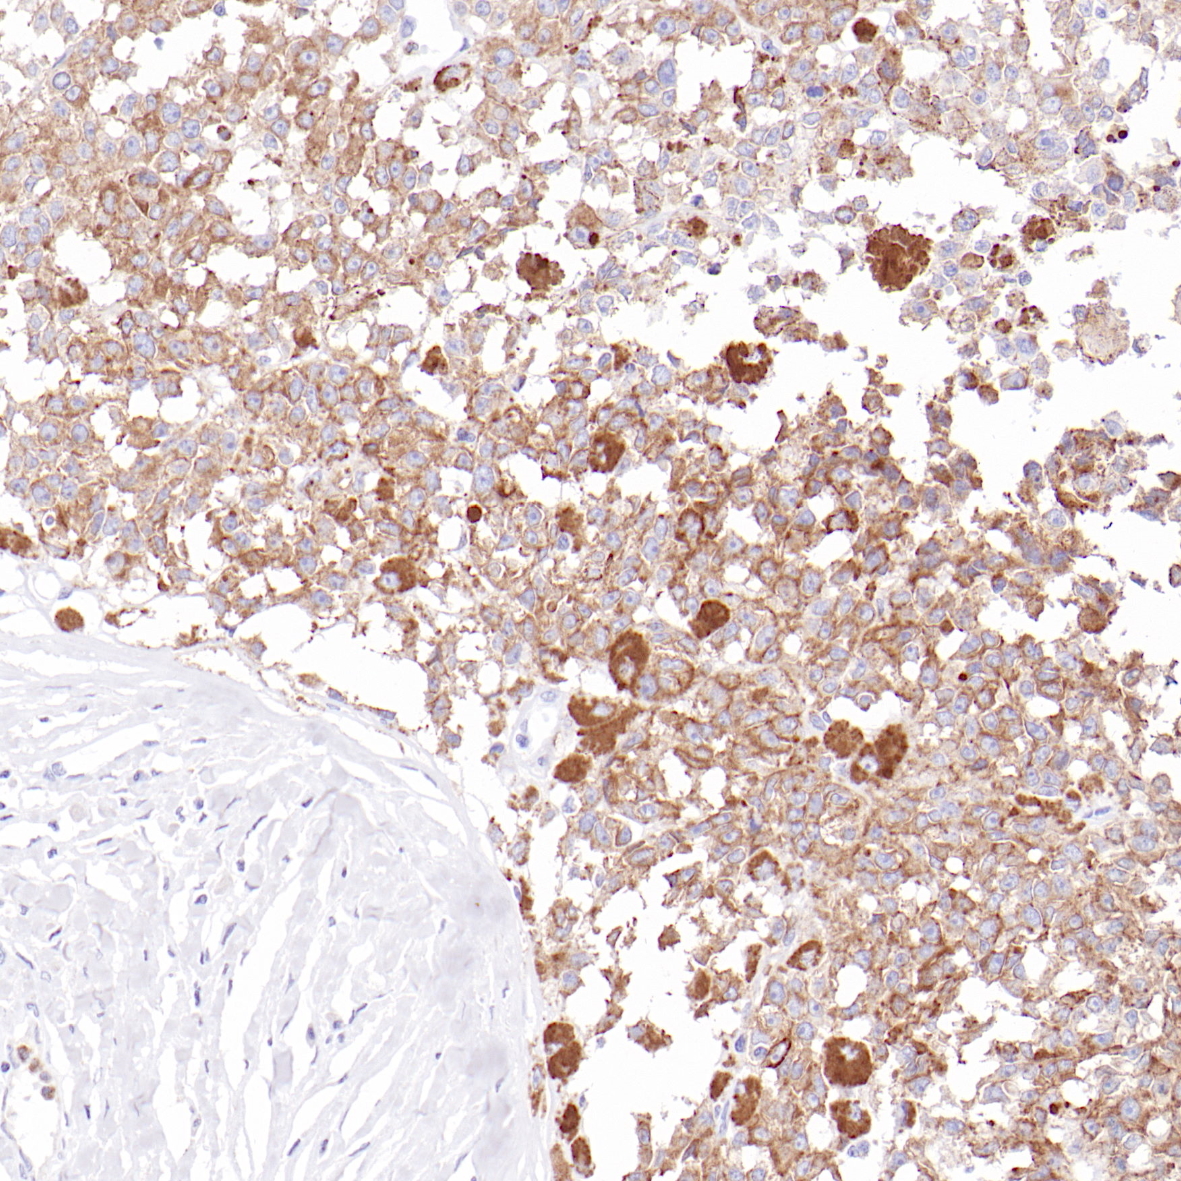

2. Caffo O , Doglioni C , Veronese S , et al. PP-9-3 Prognostic value of P21/WAF1 and P53 expression in breast carcinoma: An immunohisto-chemical study on 261 cases with long term follow up[J]. European Journal of Cancer, 1996, 32(supp-S2):1.